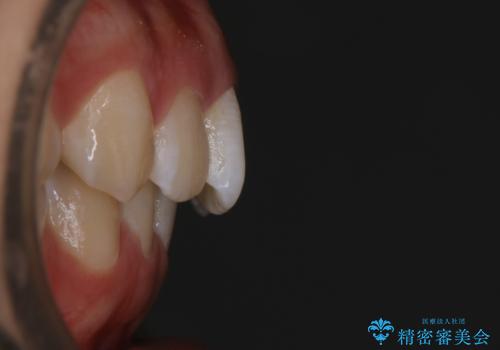

- 初診時、前歯のガタつきを主訴にご来院されました。

精密検査の結果奥歯の噛み合わせのズレからくる前歯のガタつきであることが分かり、患者様と相談した結果、全体をしっかりと治療することをご選択なさったので奥歯から動かして噛み合わせと見た目の両方を治す治療プランとなりました。

下顎の歯は幸いガタつきが少なかったため、下顎を基準とし構成する方針としました。